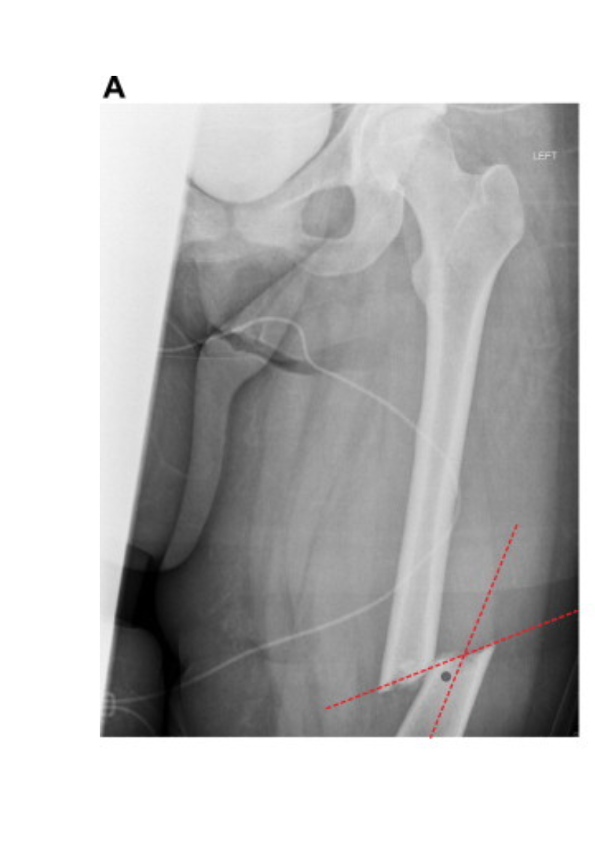

Puller螺钉精准置钉新方案